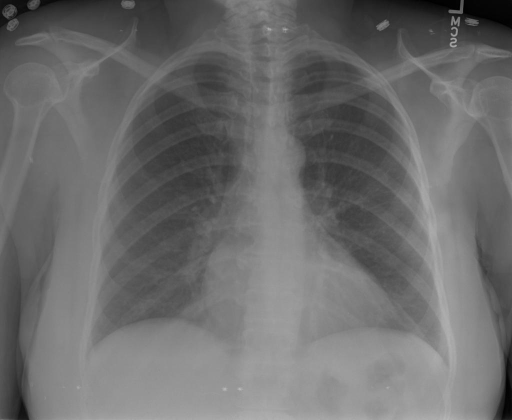

|X光影像|诊疗报告(医生)|XrayGLM|

|:-|:-|:-|

||根据X射线图像,心脏大小正常,肺部看起来很清晰。已经排除了肺炎、积液、水肿、气胸、腺病、结节或肿块的存在。该发现表明一切正常。换句话说,总体印象是胸部正常。|X光片显示,心脏大小正常。肺部没有气胸或胸腔积液的证据。骨骼结构看起来没有任何异常。总的来说,X光片表明没有发现急性心肺疾病的迹象。|